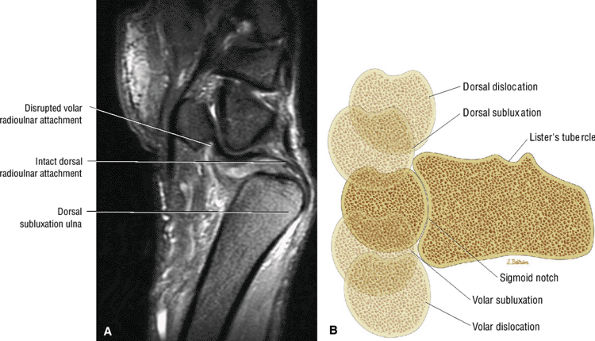

The dorsal radioulnar ligament and palmar radioulnar ligament are the primary ligamentous stabilizers of the distal radioulnar joint and on axial plane images are seen coursing on both the dorsal and volar sides of the TFC, at the level of the base of the ulnar styloid, where the ligaments insert. Tears of the dorsal radioulnar ligament are associated with volar subluxation of the ulna. Tears of the volar radioulnar ligament are associated with dorsal subluxation of the ulna. Distal radioulnar joint instability is suggested when the ulnar head is abnormally subluxed or dislocated with respect to the radius, beyond the normal range of motion allowed for pronation and supination. In addition to ligamentous injury, osseous injuries such as fractures at the base of the ulnar styloid also may lead to distal radioulnar joint instability.